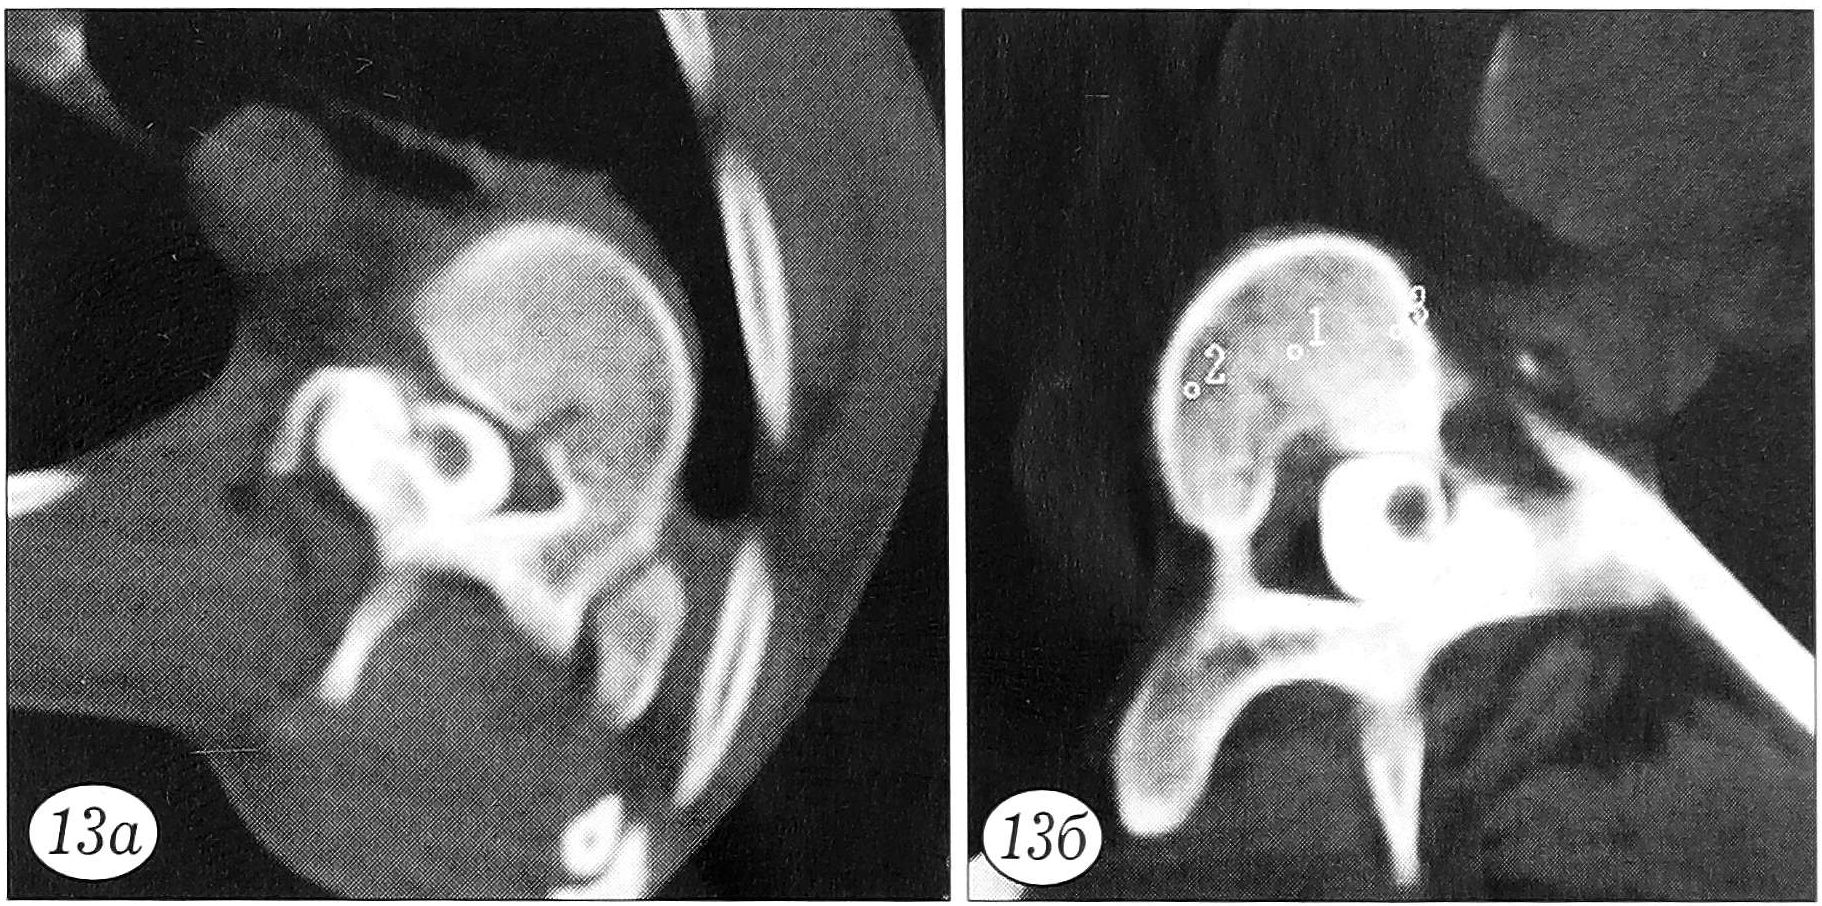

На уровне вершинного позвонка первичной дуги сколиотической деформации значимых различий в костной плотности, измеренной до и непосредственно после оперативного лечения, не обнаружено. Вместе с тем выявлена следующая закономерность: средняя величина костной плотности на вогнутой стороне деформации значимо больше, чем на выпуклой, как до, так и после оперативного лечения. Более высокая плотность костной ткани на вогнутой стороне деформации определяется и визуально при КТ (рис. 11).

Рис. 11. Вершинный позвонок первичной дуги деформации: плотность костной ткани на вогнутой стороне выше, чем на выпуклой.

Достоверных различий при сравнении показателей костной плотности в разных точках верхнего и нижнего нейтральных позвонков до и непосредственно после оперативного лечения не найдено. По вогнутой стороне деформации костная плотность нейтральных позвонков несколько ниже, чем по выпуклой, причем это различие наиболее выражено на уровне верхнего нейтрального позвонка после оперативного лечения (что, вероятнее всего, связано с изменением его положения в пространстве). В центре тела у верхнего нейтрального позвонка костная плотность значительно выше, чем у нижнего, как до, так и после оперативного лечения (практически на одинаковую величину).